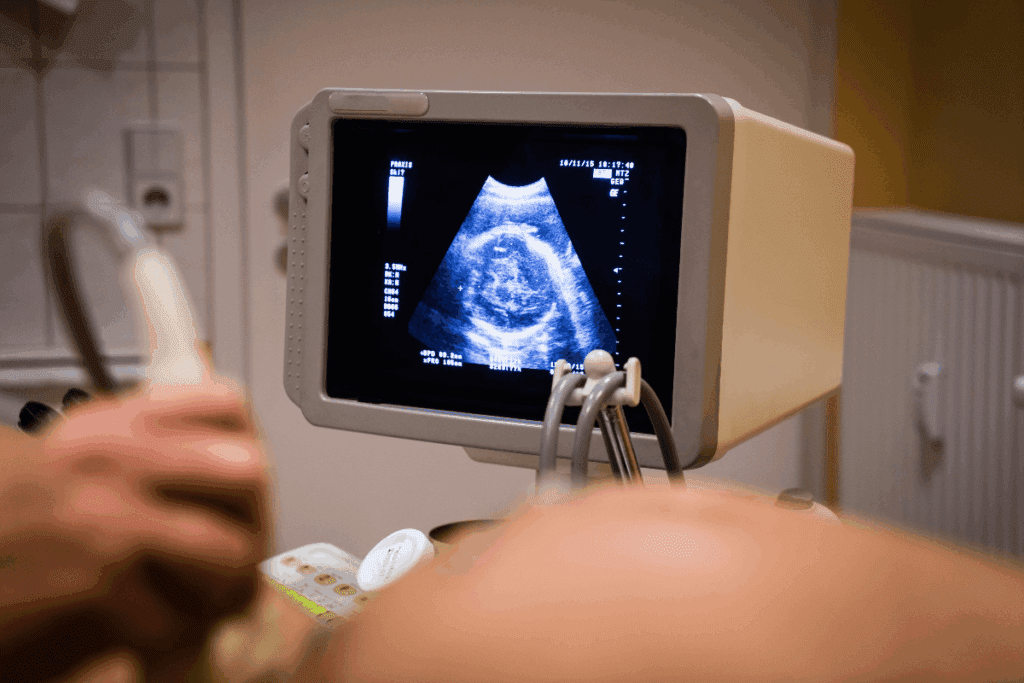

How BPD is Measured During an Ultrasound

Getting the BPD right is key to checking how a fetus is growing. We’ll show you how to measure BPD during an ultrasound. We’ll also talk about the problems that might come up.

Proper Ultrasound Technique for Accurate BPD Measurement

To get BPD right, the ultrasound tech must use a special method. They need a clear picture of the fetal head at a certain spot. The measurement goes from the outer skull edge to the inner edge.

For accurate BPD, you need:

- The right fetal head position

- Good ultrasound image quality

- The ultrasound gear set up correctly